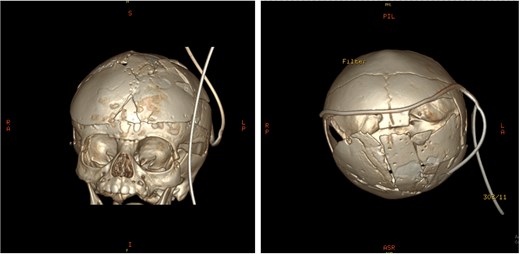

An 11-month-old female infant, born to unrelated Saudi parents, was referred to our facility with unilateral left coronal craniosynostosis, congenital microcephaly, global developmental delay, and a confirmed ZIC1 gene mutation. Comorbidities included a patent foramen ovale, aortopulmonary collateral vessel, G6PD deficiency, and gastroesophageal reflux disease (GERD). At birth head circumference was 29 cm (<first percentile), and progressive skull asymmetry and squinting were noted over time. Developmentally, she exhibited delayed gross and fine motor skills with limited object transfer. On examination, she was alert and visually tracking, with inward ocular deviation (esotropia). Head circumference was 37 cm (<first percentile) with anterior plagiocephaly and towering of the left frontal region (Fig. 1). Pupils were equal and reactive. Fundoscopy and cranial nerve examinations were unremarkable. Gross motor power was within normal limits, except for moderate lower limb spasticity. 3D reconstruction computed tomography (CT) confirmed premature fusion of the left coronal suture with subtle elevation of the superolateral orbital rim, indicating harlequin sign (Fig. 1). Brain CT showed corpus callosum agenesis, colpocephaly, mild ventriculomegaly, right cerebellar and pontine hypoplasia, and a large cisterna magna, consistent with the reported ZIC1-related malformation spectrum (Fig. 2). Given the progressive deformity and concerns of increased intracranial pressure that might be partially contributing to her neurodevelopmental delay, anterior cranial vault expansion with fronto-orbital advancement was performed jointly by the neurosurgery and plastic craniofacial teams (Fig. 3). Intraoperatively, left-sided dural tension was appreciated, indicating localized increased intracranial pressure. The orbital bandeau was reshaped and advanced, achieving immediate cosmetic improvement (Fig. 4). The patient tolerated the surgery well and recovered uneventfully. At her 4-month follow-up, she showed developmental progress including standing without support, purposeful hand use, and verbalization (“Baba”). At 6-month follow-up, brain CT revealed areas of bone resorption which led to the placement of a ventriculo-peritoneal shunt (Fig. 5). The known association of ZIC1 mutation with tethering of the cord prompted spinal magnetic resonance imaging (MRI) screening. Positive findings indicated an untethering procedure, which was successfully done (Fig. 6).

Post-operative 3D reconstruction CT showing skull shape correction and cosmetic results.